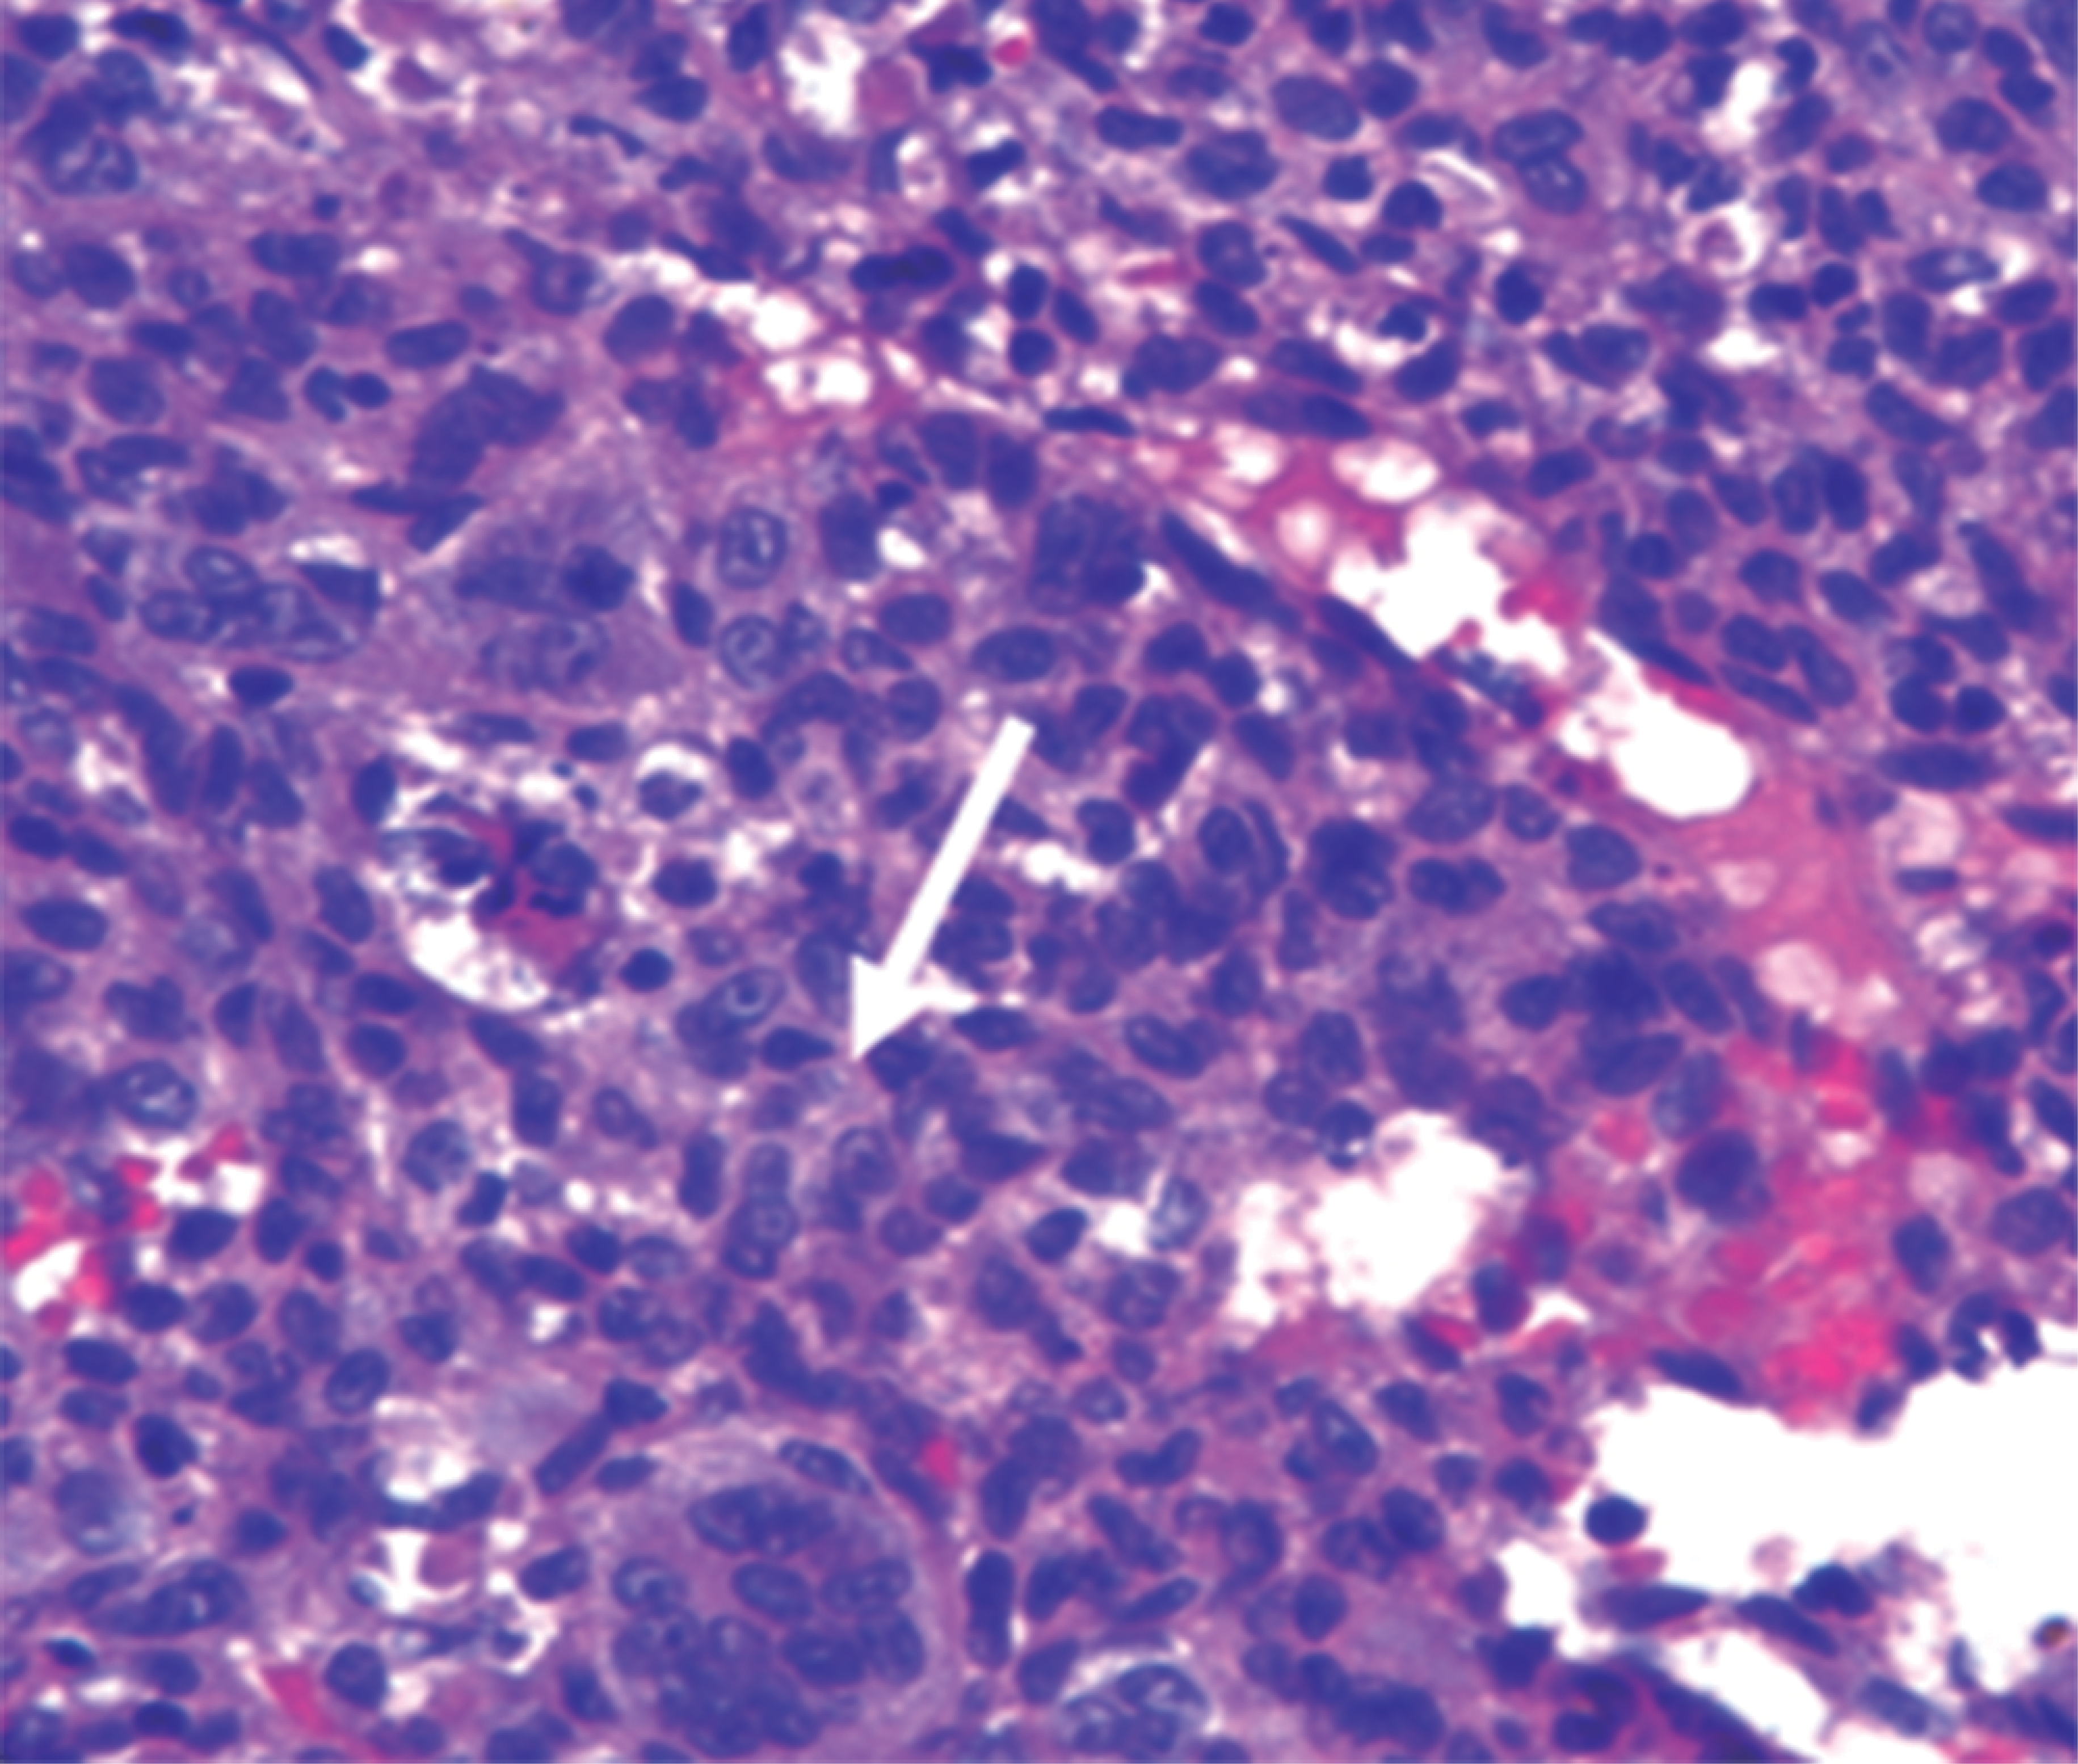

Paciente masculino de nueve años, sin antecedentes heredofamiliares relevantes o presencia de comorbilidades previas, inicia con dolor a nivel dorsal, el cual es tratado conservadoramente, remitiendo de forma parcial; posteriormente presenta alteraciones de la marcha, por lo que acude a su hospital general de zona donde se le integra el diagnóstico de cerebelitis y se establece manejo conservador, con mejoría parcial. Es valorado por el Servicio de Neurocirugía Pediátrica en el Hospital Centro Medico "La Raza" por persistencia de alteraciones en la marcha, a la cual se agrega paraparesia progresiva y dolor torácico, integrándose diagnóstico de probable síndrome de Guillain-Barré, por lo que se le solicita resonancia magnética y tomografía, donde se aprecia a nivel de T4 tumoración con crecimiento intrarraquídeo extradural que condiciona compresión de 50% del canal medular (Figura 1). Se realiza biopsia y resección intralesional del tumor, con resultado de esta biopsia de tumor de células gigantes con componente de quiste óseo aneurismático y es egresado a su domicilio (Figura 2). Sin embargo, el paciente es reingresado al servicio de neurocirugía pediátrica por persistencia de paraparesia, por lo que se decide realizar nueva resonancia magnética en la que se observa colapso vertebral, cifosis segmentaria, por lo que es enviado al Hospital de Traumatología y Ortopedia de Lomas Verdes.

Resultado histopatológico en el que se muestran los hallazgos característicos de este tipo de neoplasias, con células gigantes, multinucleadas con la cual se realiza diagnóstico definitivo (Figura 2).